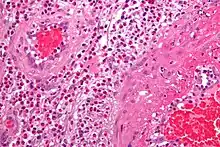

- The definite diagnosis of vasculitis is established after a biopsy of involved organ or tissue, such as skin, sinuses, lung, nerve, brain, and kidney. The biopsy elucidates the pattern of blood vessel inflammation.

- Some types of vasculitis display leukocytoclasis, which is vascular damage caused by nuclear debris from infiltrating neutrophils.[12] It typically presents as palpable purpura.[12] Conditions with leucocytoclasis mainly include hypersensitivity vasculitis (also called leukocytoclastic vasculitis) and cutaneous small-vessel vasculitis (also called cutaneous leukocytoclastic angiitis).